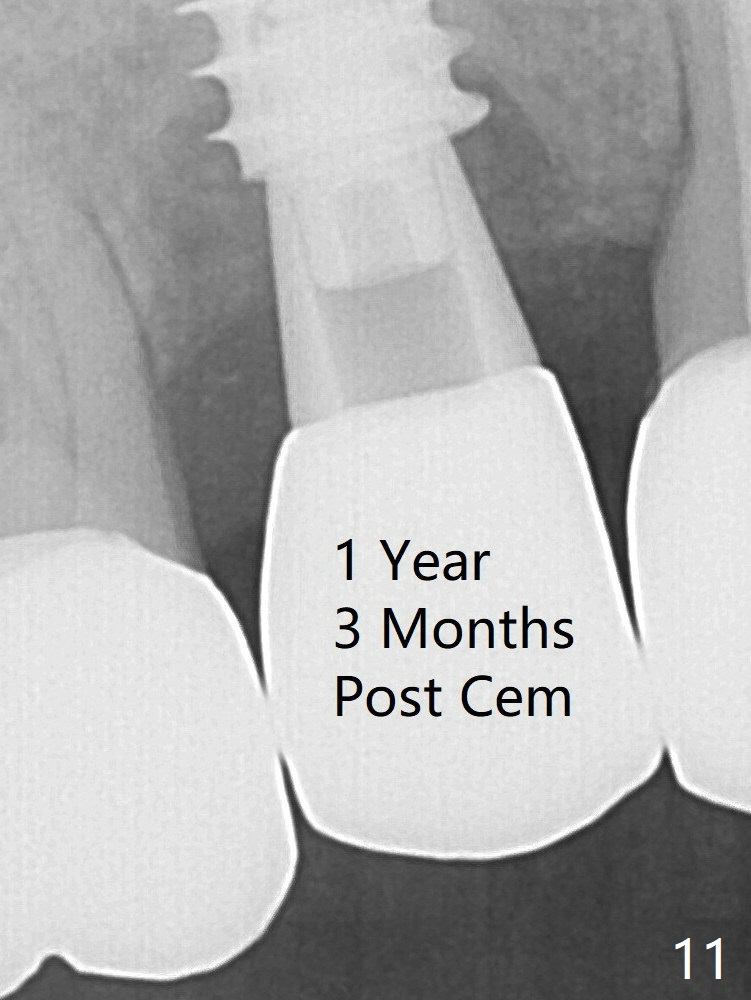

To reduce the gap and periimplantitis, a 5x11 mm IBS implant is placed with insertion torque > 50 Ncm after further osteotomy using Magic Drills (Fig.4). Following placement of 5.5x4(4) mm abutment (A), a splinted provisional is fabricated at #3 and 4. The provisional is stable 3 months postop (Fig.7). Bone graft appears to remain between the implant fins (arrows). The bone density of the bone graft between the implant fins increases 4.5 months postop (Fig.9). The bone density appears to reach the normal value (same as that of the nearby bone) 1 year 3 months post cementation (Fig.11).